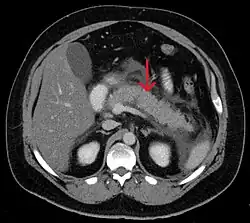

A contrast-enhanced CT scan is usually performed more than 48 hours after the onset of pain to evaluate for pancreatic necrosis and extrapancreatic fluid as well as predict the severity of the disease. CT scanning earlier can be falsely reassuring.[34]